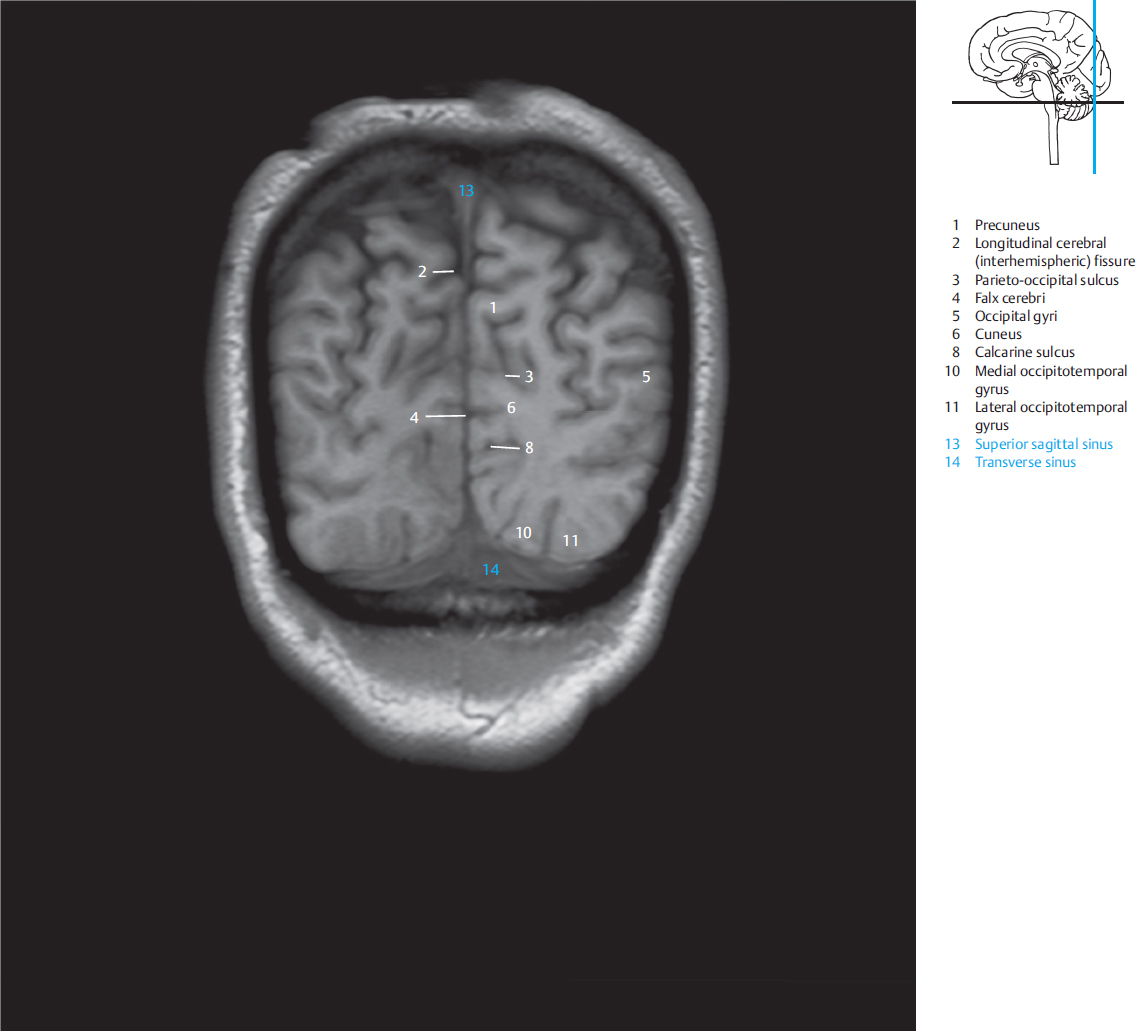

最新人気 MRI and CT Atlas of Correlative Imaging in Otolaryngology 洋書の詳細情報

MRI and CT Atlas of Correlative Imaging in Otolaryngology。Pocket Atlas of Sectional Anatomy, Computed Tomography and。Eagle-449: A volumetric, whole-brain compilation of brain。コウノトリ育むお米 こしひかり 5kg。

下記に商品説明や配送料・配送方法・注意事項等の説明がございます。Head and Neck | Clinical Gate。CT & MRI Pathology: A Pocket Atlas, Third Edition。

■商品名■ MRI and CT Atlas of Correlative Imaging in Otolaryngology Flanders, Adam E、 Rao, Vijay M; Tom, Barry M ■出版社■ CRC Press ■著者■ Flanders Adam E ■発行年■ 1992/01/01 ■ISBN10■ 1853170372 ■ISBN13■ 9781853170379 ■コンディションランク■ 可 コンディションランク説明 ほぼ新品:未使用に近い状態の商品 非常に良い:傷や汚れが少なくきれいな状態の商品 良い:多少の傷や汚れがあるが、概ね良好な状態の商品(中古品として並の状態の商品) 可:傷や汚れが目立つものの、使用には問題ない状態の商品 ■コンディション詳細■ 当商品はコンディション「可」の商品となります。Eagle-449: A volumetric, whole-brain compilation of brain。。水濡れ防止梱包の上、迅速丁寧に発送させていただきます。 |